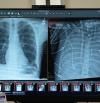

Sobreviure sense pulmons: un sistema artificial permet esperar un trasplantament

Desenvolupen una màquina que substitueix temporalment les funcions pulmonars